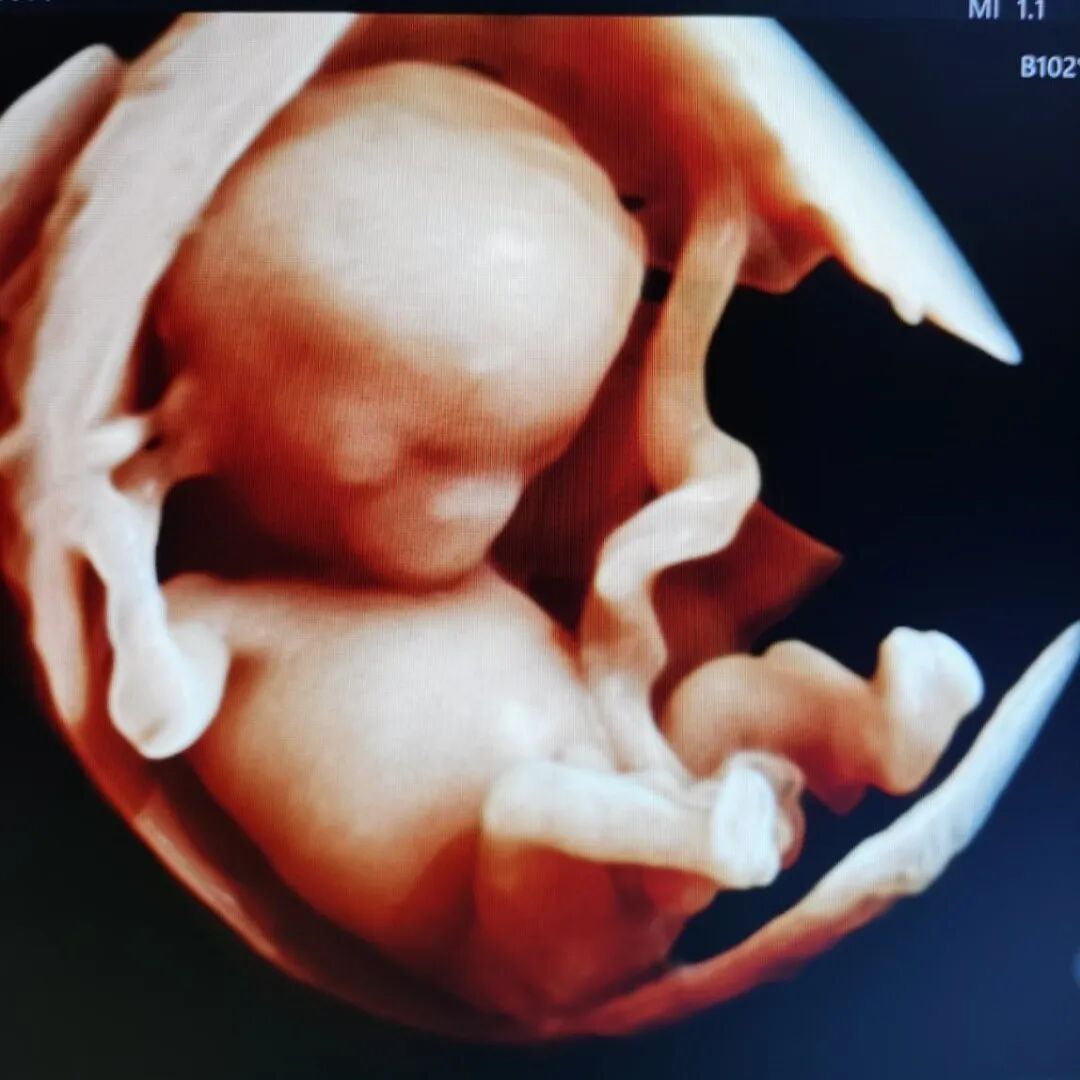

二、高清画质,成像效果惊人

相较普通四维彩超,E10的高清画质堪比IMAX电影大片!

过去的四维彩超能看到宝宝吐舌头、吃手指,但常常看到胎宝宝就像个“小泥人”,只能看看大致轮廓;E10四维彩超,可以实现您与宝宝的超高清“隔空对视”,直接观察他们的一举一动、乖巧秀容,包括:皱眉、微笑、打哈欠、吸吮等,提前享受将为人父人母的喜悦。